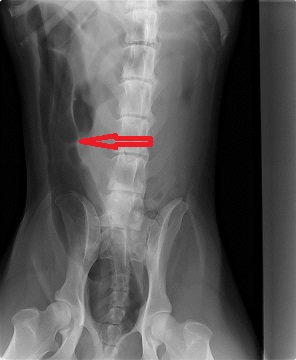

Op de röntgenfoto bleek dat er heel veel gas in een groot deel van de darmen en de maag aanwezig was. Gas op de foto toont zich als een zwarte vlek (zie rode pijlen).

De 2e röntgenfoto is genomen terwijl Lee op zijn rug lag. Op deze foto ziet u heel duidelijk een zwarte streng, een gedeelte van de darm is volledig gevuld met gas. Dit duidt absoluut op een verstopping in de darmen. Het advies was dan ook om Lee direct onder narcose te brengen en in de buik te gaan kijken wat er aan de hand was.